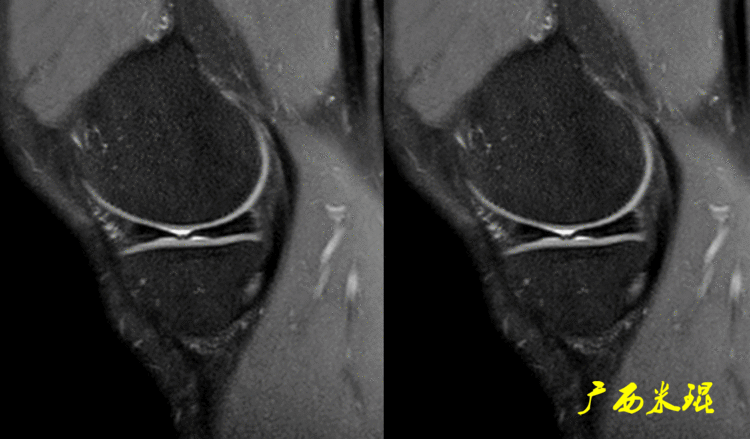

二、半月板损伤MR诊断的陷阱1:裙边样半月板(1)正常半月板的裙边正常半月板体部的游离缘有时候可以“变形”呈“裙边样或荷叶边样”,MR以及关节镜手术中都能够见到,特别是内侧,可能与内侧半月板游离缘更菲薄,而滑膜缘又被半月板胫骨韧带牢靠固定有关,这种改变可以通过改变膝关节的屈伸状态而消失。

有时候我们在MR上看见内侧半月板信号正常,半月板体部呈单裙边改变,周围软骨正常。

有时候半月板体部呈双裙边改变,周围软骨正常,以上这样的情况半月板都是正常的,不是损伤。